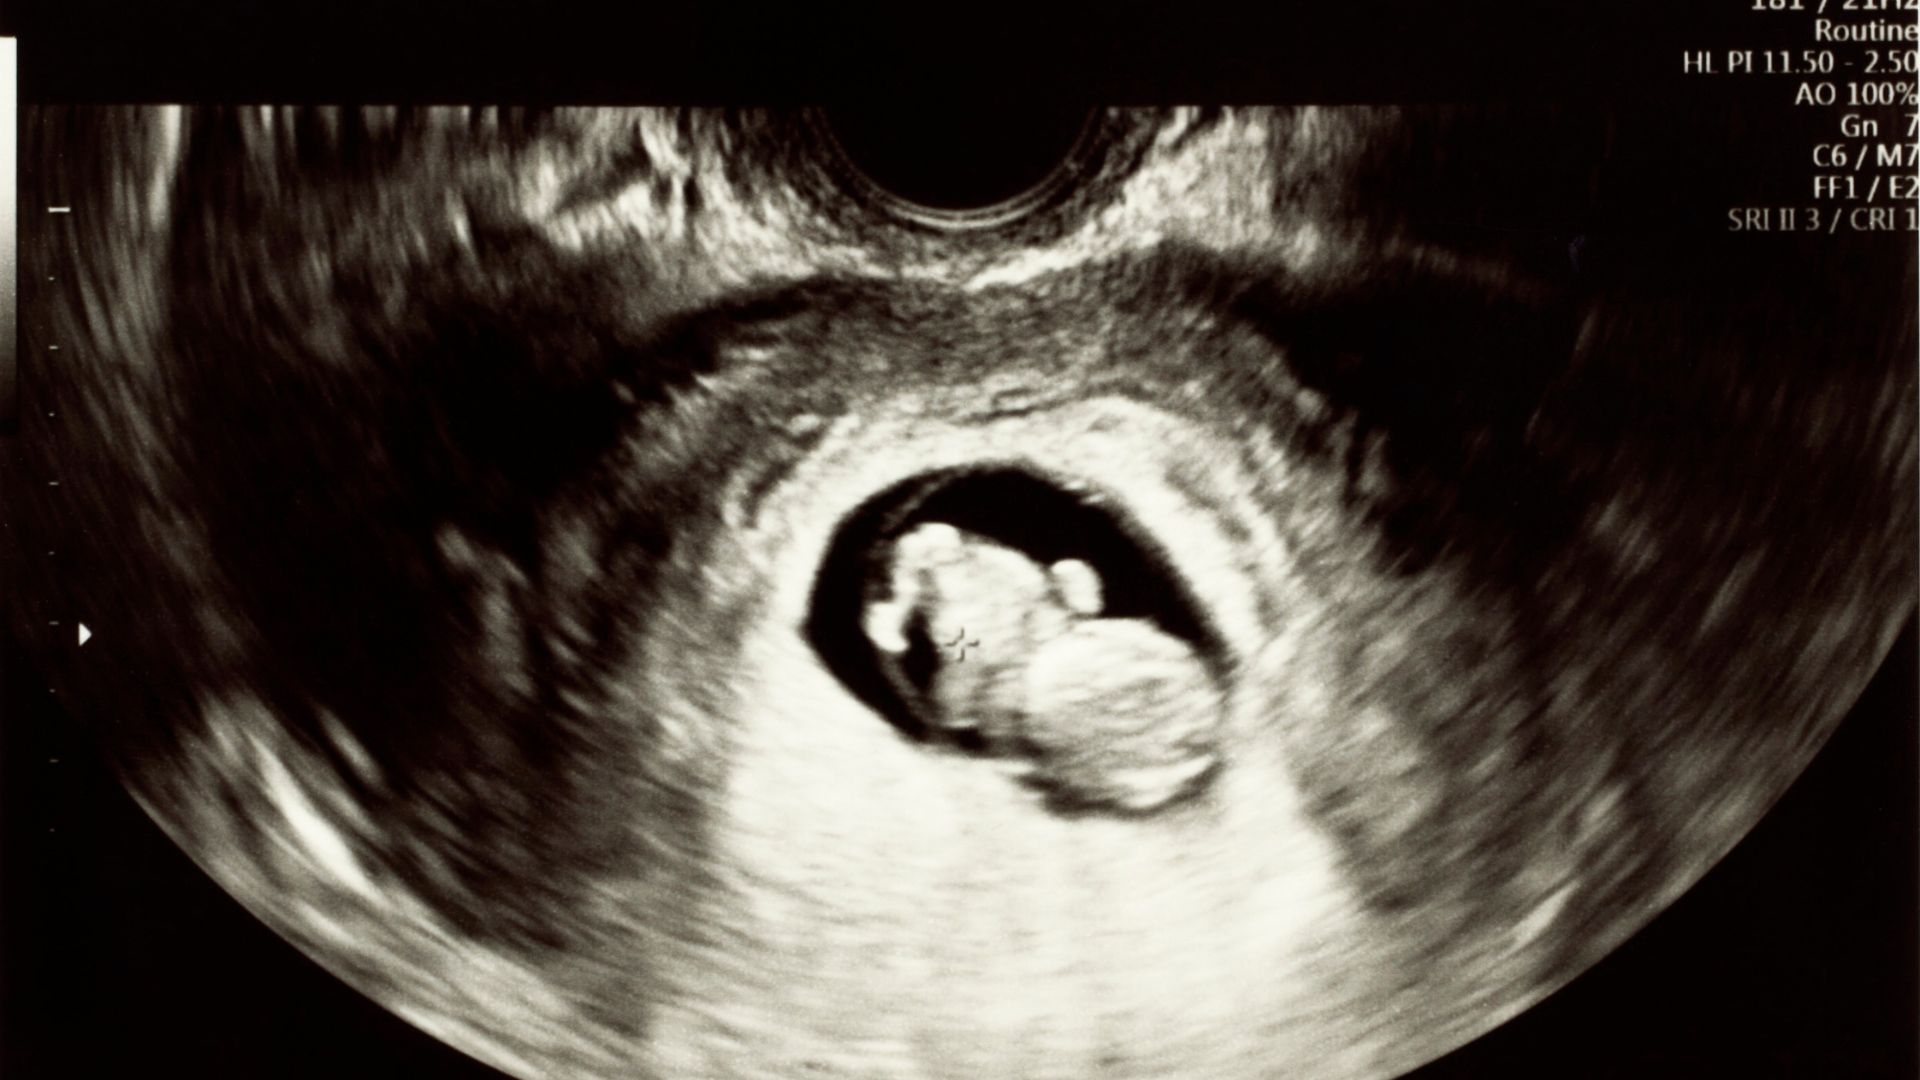

Trong tam cá nguyệt đầu tiên, sàng lọc trước sinh đóng vai trò quan trọng nhằm phát hiện sớm nguy cơ bất thường nhiễm sắc thể. Double test là xét nghiệm được chỉ định phổ biến ở giai đoạn 11 - 13 tuần thai. Tuy nhiên, khi nhận kết quả thuộc nhóm nguy cơ cao, nhiều gia đình rơi vào trạng thái hoang mang, thậm chí nghĩ ngay đến những kịch bản xấu nhất.

Double test được thực hiện từ tuần 11 đến 13 tuần 6 ngày của thai kỳ. Xét nghiệm này bao gồm:

- Siêu âm đo độ mờ da gáy;